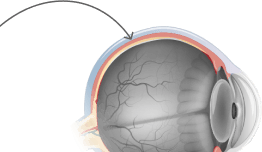

Lutexid tiene un efecto beneficioso sobre los músculos oculares: previene la hipertonicidad, alivia la fatiga, ayuda al cristalino a enfocar correctamente y garantiza una imagen nítida y clara.

Lutexid ayuda a aumentar el número de células sensibles a la luz, lo que mejora la claridad, la nitidez y la agudeza de la visión, y garantiza una correcta reproducción de los colores y una excelente visión crepuscular y lateral.